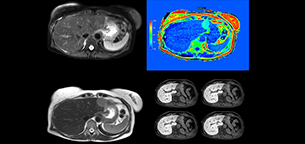

mDIXON Quant is a simple sequence to include in routine liver MRI

“We have performed a study comparing mDIXON Quant fat percentages with results from histopathology. The correlation with different histologic methods was very good and also the correlation with MR spectroscopy was far above 0.9 – a nearly perfect correlation,” says Dr. Kukuk.

“So, this fast mDIXON Quant sequence allows us to diagnose, quantify, and follow up – that’s the real advantage. Our gastroenterologists were easily convinced, as they are well aware of the limitations of ultrasound and the risks of liver biopsy.”

“Also patients appreciate receiving the quantitative diagnosis and changes seen in follow-up exams during therapy.”

“I would recommend acquiring mDIXON Quant routinely in liver MRI exams. It is fast, easy to use, and has been well evaluated [2,3]. The time investment is low and the benefit is high.”

Non-invasive liver fat quantification in a breathhold with mDIXON Quant

“Fatty liver disease is a common condition. Studies found a prevalence of non-alcoholic fatty liver disease in up to 44% in the general European population [1]. Liver fat cannot be quantified by ultrasound or CT, so biopsy has been the way to quantify fatty liver disease so far,” says Dr. Kukuk. “mDIXON Quant now allows non-invasive quantification of liver fat, which is valuable for both diagnosis and follow-up during dietary changes or therapy, for instance in hepatitis C.”

“The mDIXON Quant fat fraction maps provide quantitative information and also anatomical detail. The sequence is fast, usually taking about 16 seconds, which is just a breath hold for most patients. It definitely improves our efficiency.”